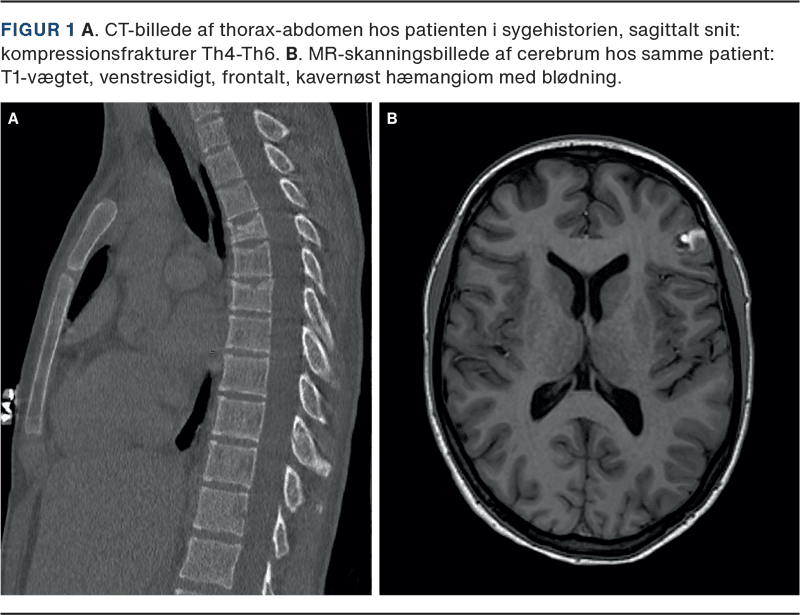

En 19-årig, tidligere rask kvinde blev om natten indlagt i akutmodtagelsen efter krampeanfald i hjemmet. I ambulancen var hun smerteklagende og postiktal, og hun fik et nyt krampeanfald. Ved ankomst var hun svært smerteforpint og postiktal. Arteriepunktur viste: pH 7,19, pCO2 5 kPa, pO2 7,7 kPa, baseoverskud –12,3 mmol/l og laktatkoncentration 9,2 mmol/l. Objektiv undersøgelse var uden nakke-ryg-stivhed eller petekkier, intet Kernigs symptom, egale pupiller, men betydelig bankeømhed i de torakale ryghvirvler. Der blev foretaget lumbalpunktur og startet steroid- og antibiotisk behandling i meningitisdoser. Cerebrospinalvæsken fremstod klar og med normale tal. CT af thorax-abdomen viste kompressionsfrakturer i Th4, Th5 og Th6 (Figur 1 A). Patienten blev overflyttet til en intensivafdeling, hvor der blev målt en moderat forhøjet kreatinkinasekoncentration på 4.800 E/l og en myoglobinkoncentration på 810 μg/l. I de efterfølgende dage steg disse værdier til henholdsvis 26.500 E/l og 3.160 μg/l, hvor patienten var blevet loadet med levetiracetam i dosis 60 mg/kg med henblik på at forebygge yderligere krampetilfælde.

Patienten blev efterfølgende overflyttet til et universitetscenter, hvor MR-skanning af cerebrum viste mindre, kavernøst hæmangiom med venstresidig, frontal blødning og central forkalkning (Figur 1 B). Dette fund blev vurderet som epileptogen årsag til patientens anfald. Patientens rabdomyolyse blev behandlet med intravenøs indgift af krystalloider over de næste dage, og rabdomyolysen rettede sig spontant uden tegn til nyrepåvirkning i forløbet. Der blev ikke observeret yderligere krampetilfælde efter første krampeanfald. En efterfølgende DEXA-skanning viste normal knogledensitet, og blodprøver for D-vitamin, parathyroideahormon og calcium var alle i normalområdet. Kompressionsfrakturerne blev konservativt behandlet med smertestillende medicin og mobilisering. Efter fem måneder gennemgik patienten en vellykket operation med resektion af det kavernøse hæmangiom, og hun var siden velbefindende uden anfald.